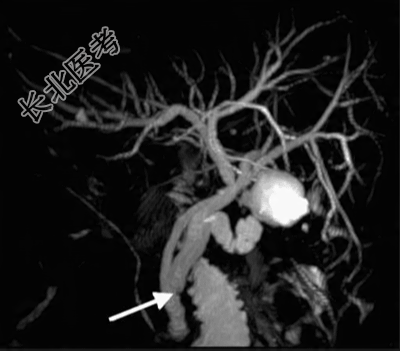

腹部超声检查显示胆囊床处卷曲囊性结构增大,与胆囊残留物的增加一致,未发现胆道结石的超声证据。行磁共振胰胆管造影(MRCP)进一步评估胆管树,结果发现胆囊管残端结石,伴总胆管(CBD)受压以及上游胆管扩张。

由于患者疑似急性上行性胆道炎,隧开始静脉应用哌拉西林/他唑巴坦治疗。内镜逆行胰胆管造影术(ERCP)中胆道造影显示远端插入的长胆囊管残端充盈缺损,提示残留结石导致部分胆道梗阻。

隧行括约肌切开术,置入9-12 mm球囊探查总胆管,在胆囊管插入处遇中度阻力。术后CBD内未发现充盈缺损也未发现结石。随后选择性进行胆囊管置管并置入球囊,取出一较大胆管结石。球囊胆管造影显示整个胆道,包括胆囊管残端无残余充盈缺损,胆汁和造影剂引流良好,最终确诊为胆囊切除术后Mirizzi综合征(PCMS)。